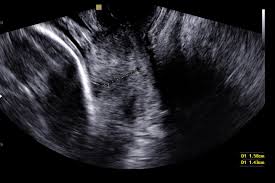

Cervical Length Scan

- Done via transvaginal ultrasound

- Measures cervix length

- A short cervix increases risk of preterm birth